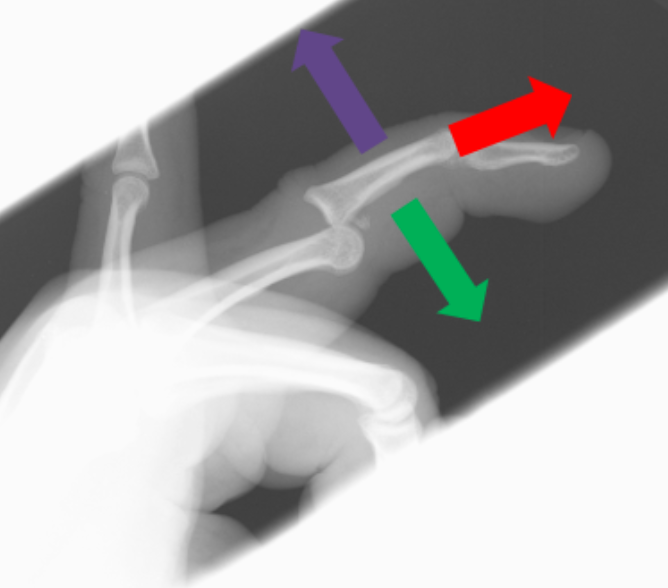

Dorsal PIP Dislocation

1. Disengage by pulling in the direction of the dislocation to disengage form the articular plate. In this case pull dorsally (purple arrow)

2. Firmly and smoothly apply longitudinal traction (red arrow)

3. Flex into place (green arrow)

These steps should all be done in one smooth, swift and rapid motion.